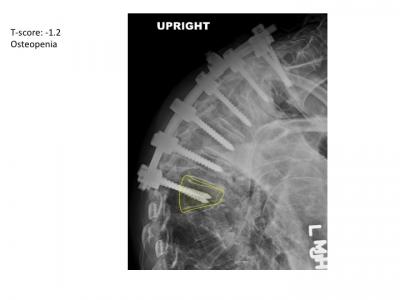

A new study indicates that many patients undergoing spine surgery have low levels of vitamin D, which may delay their recovery.

In a study of 313 patients undergoing spinal fusion surgery, orthopaedic surgeons at Washington University School of Medicine in St. Louis found that more than half had inadequate levels of vitamin D, including one-fourth who were more severely deficient.

Vitamin D helps with calcium absorption, and patients with a deficiency can have difficulty producing new bone. They are at risk for a condition called osteomalacia. Unlike osteoporosis or osteopenia, which result from low bone mineral density, osteomalacia interferes with new bone formation.

All the patients in the study had spinal fusion surgery. In that procedure, surgeons remove discs between two or more vertebrae. The bones in the spine are then attached with hardware and treated with growth factors. As the spine heals, new bone begins to form, and the vertebrae fuse together.